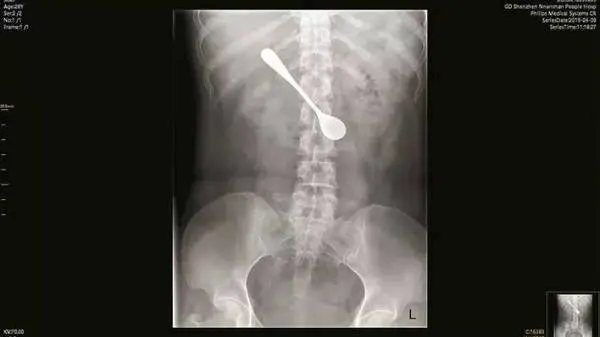

هنگامی که او به بیمارستان مراجعه کرد پزشکان فورا از رادیولوژی استفاده کرده و تصویر قاشق را که در دوازدهه وی گیر کرده بود، مشاهده کردند. دکتر سان تینگجی گفت:همانطور که قاشق در موقعیت تا حدودی افقی قرار داشت، ما آن را به دقت ، طوری تنظیم کردیم تا قبل از بیرون آمدن، عمودی نشود.